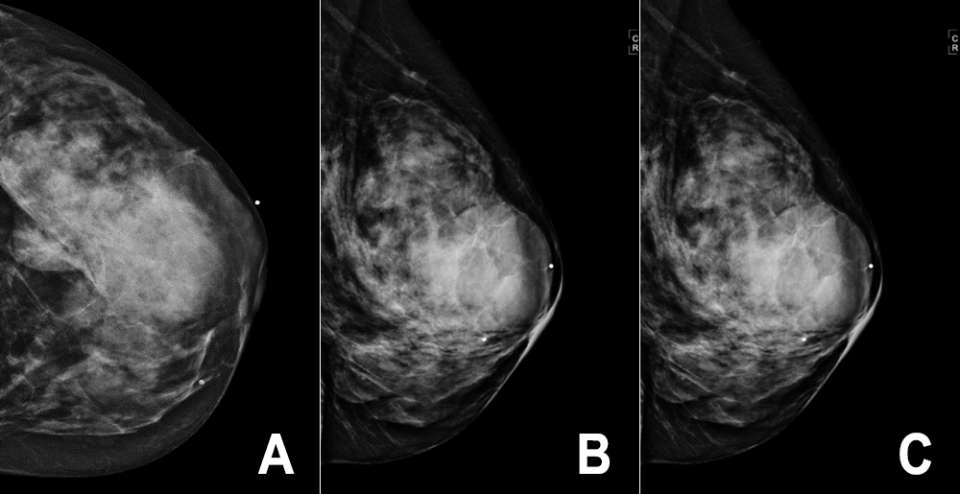

Case: Breast Sarcoma Figure 3

Figure 3: PET/CT of the above breast sarcoma (see Figure 1 and 2) demonstrates intense FDG uptake within the mass.

While PET/CT is more likely used to evaluate extent of disease in a patient with a known diagnosis, breast sarcomas may demonstrate avid FDG uptake6. (Figure 3).